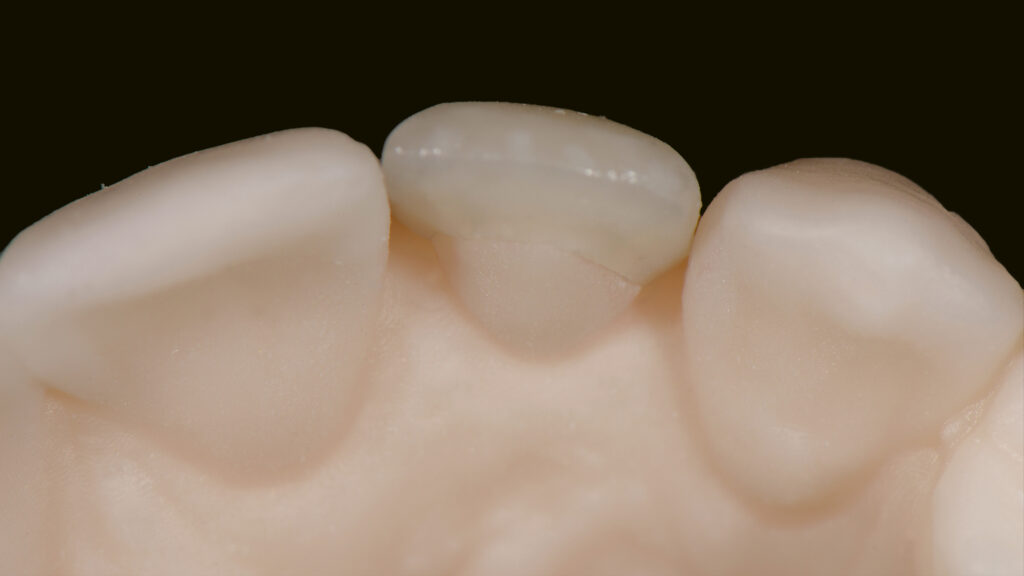

Vita Ambria (Vita Zahnfabrik, Bad Säckingen) ist ein mit Zirkonoxid verstärktes Lithiumdisilikat mit hoher Festigkeit (>500 Mpa), das in der Presstechnik verarbeitet wird. Die Keramik eignet sich besonders für die effiziente Herstellung von hochästhetischen, langlebigen Restaurationen wie Overlays und Teilkronen. Das Presskeramik-System enthält Presspellets in den Transluzenzstufen T (transluzent) und HT (hochtransluzent) (Abb. 15). Ein Vorteil ist, dass die aus Vita Ambria gepresste Restauration vollanatomisch und monolithisch bemalt und glasiert oder mit der Verblendkeramik Vita Lumex AC (Vita Zahnfabrik) fertiggestellt werden kann. Nach dem Modellieren des hauchdünnen Käppchens (Abb. 16) und dem Pressen erfolgt das Ausbetten der Keramikschale. Die minimale Reaktionsschicht kann mit geringem Druck (2 bar) abgestrahlt werden, so dass passgenaue Ergebnisse effizient erzielt werden. Da die Schale in der Farbe A1 (HT-Rohling) gepresst wurde (Abb. 17) und die Schichtstärke nur 0,2 bis 0,3 mm beträgt, wirkt sie sehr transluzent (Abb. 18). Es folgt die Verblendung mit Vita Lumex AC. Hier zeigt sich ein weiterer Vorteil für die Umsetzung dieses Falles. Denn die Verblendkeramik kann auch auf Zirkonoxidgerüsten verwendet werden. Vita Lumex AC ist eine leutzitverstärkte Glaskeramik zur Verblendung vollkeramischer Gerüste aus Zirkondioxid-, Lithiumdisilikat- und Feldspatkeramik sowie zur Herstellung von keramischen Veneers.

Individuelle Minimal-Schichtung

Vor dem Brand wird etwas „Smoky White“ auf das Käppchen gestreut, um den Helligkeitswert zu erhöhen (Abb. 19). Eine Aufnahme unter UV-Licht verdeutlicht die Fluoreszenz der gestreuten Keramikmasse (Abb. 20). Die Vorteile der Streutechnik sind keine Erfindung von uns. Vielmehr hat uns unser Kollege und Freund Oliver Brix darauf hingewiesen, wie solche Käppchen vorbehandelt werden können, um eine bessere Tiefenwirkung zu erzielen. Für den ersten Hauptbrand wird interdental/zervikal eine dünne Schicht Effekt-Chroma aufgetragen und die anatomische Form mit etwas Dentin A1 ergänzt. Nach einem Cutback (Abb. 21) des inzisalen Drittels wird eine Mischung aus Schneidemasse sowie „Light“- und „Waterdrop“-Masse (tranzluzente blau/graue Masse) im Verhältnis 1:1 als Schneideteller aufgebaut (Abb. 22). Auf Opakdentin wurde aus Platzgründen und zur besseren Sichtbarkeit der natürlichen Zahnfarbe verzichtet. Die dünne Kappe bietet genügend Transluzenz und Helligkeit, um mit einer dünnen Schicht Verblendkeramik die gewünschte Helligkeit, Sättigung und Farbe zu erzielen. Die Individualisierung der Inzisalkante erfolgt mit der wärmeren und fluoreszierenden Keramik „Saffron“, die mit Interno Liquid angemischt wird (Abb. 23). Vorteil dieser Mischung ist, dass das Liquid die Masse besser einfärbt und so die Sättigung mit bloßem Auge kontrolliert werden kann. Außerdem ist die angemischte Masse sehr plastisch und lässt sich kontrolliert auf den Inzisalteller auftragen. Zur Imitation von weißlichen Kalkflecken wird „Smoky White“ mit Interno Liquid angemischt und mit dem Pinsel in die Schneidemasse eingearbeitet (Abb. 24). Nach dem ersten Brand der minimalen Schichtung sind alle Merkmale gut sichtbar. Wie in der Natur kommen sie aus der Tiefe (Abb. 25 bis 27).

Beim zweiten Brand wird die minimale Schichtung mit „Tranzluzent Clear“ ergänzt, um eine Art Filtereffekt zu erzeugen. Dies simuliert einen 3D-Effekt (Envelope-Technik), der feine Details aus der Tiefe erscheinen lässt. Der distale Kontaktpunkt wird mit etwas Dentin aufgebaut (Abb. 28). Das Gerüst wurde aus einem HT-Rohling gepresst, um einen Chamäleoneffekt zu erzielen. Dies ist mit transparenten Massen gut möglich. Dieses Vorgehen sollte jedoch nur dann gewählt werden, wenn keine Farbveränderungen (z. B. bei verfärbten Zähnen) gewünscht sind. Grundsätzlich erspart ein detaillierter Auftrag der Keramikmassen ein aufwendiges Beschleifen der Keramikrestauration im Nachhinein (Abb. 29).

Nach dem zweiten Brand wird die Form kontrolliert, um dann auf dem ungesägten Modell die Kontaktflächen und die Ausbildung der Leisten zu überprüfen (Abb. 30 und 31). Die labialen und distalen Leisten definieren die Dimension und die Grundform des Zahnes (Abb. 32). Abschließend wird das Veneer fertiggestellt; es erfolgt ein Glanzbrand (Abb. 33). Die Feinabstimmung des Glanzgrades bei Einzelkronen ist ebenso wichtig wie alle anderen Parameter (z. B. Helligkeit, Sättigung, Farbe). Um einen matten Glanz zu erzielen, wird in diesem Fall eine kürzere Haltezeit von 30 Sekunden und eine niedrigere Endtemperatur von 745°C gewählt. Ein zu hoher Glanzgrad würde den künstlichen Zahn „verraten“. Die Oberflächenstruktur ist patientenspezifisch. In die Zahnoberfläche werden Perkymatien – feine horizontale Wachstumsrillen – eingearbeitet, die mit den Jahresringen eines Baumes vergleichbar sind. Es ist wichtig, die Oberflächentextur dem Restgebiss anzupassen. Auf der Oberfläche entstehen durch die Lichtstreuung der Mikrostruktur bestimmte Lichtreflexe (Abb. 34). Die Natur macht es vor: Durch die Beschichtung der keramischen Restauration mit Goldpulver werden die natürlichen Makro- und Mikrostrukturen deutlich sichtbar (Abb. 35). Zudem macht eine „polar_eyes“-Aufnahme (Kreuzpolfilter) die keramische Schichtung im Zahninneren sichtbar (Abb. 36). Die Aufnahme zeigt die natürliche Fluoreszenz und insbesondere die mit „Smoky White” erzielte Imitation der Kalkflecken (Abb. 37). Dem Einsetzen des Keramikveneers 22 schließt sich die implantologische Therapie regio 12 an.